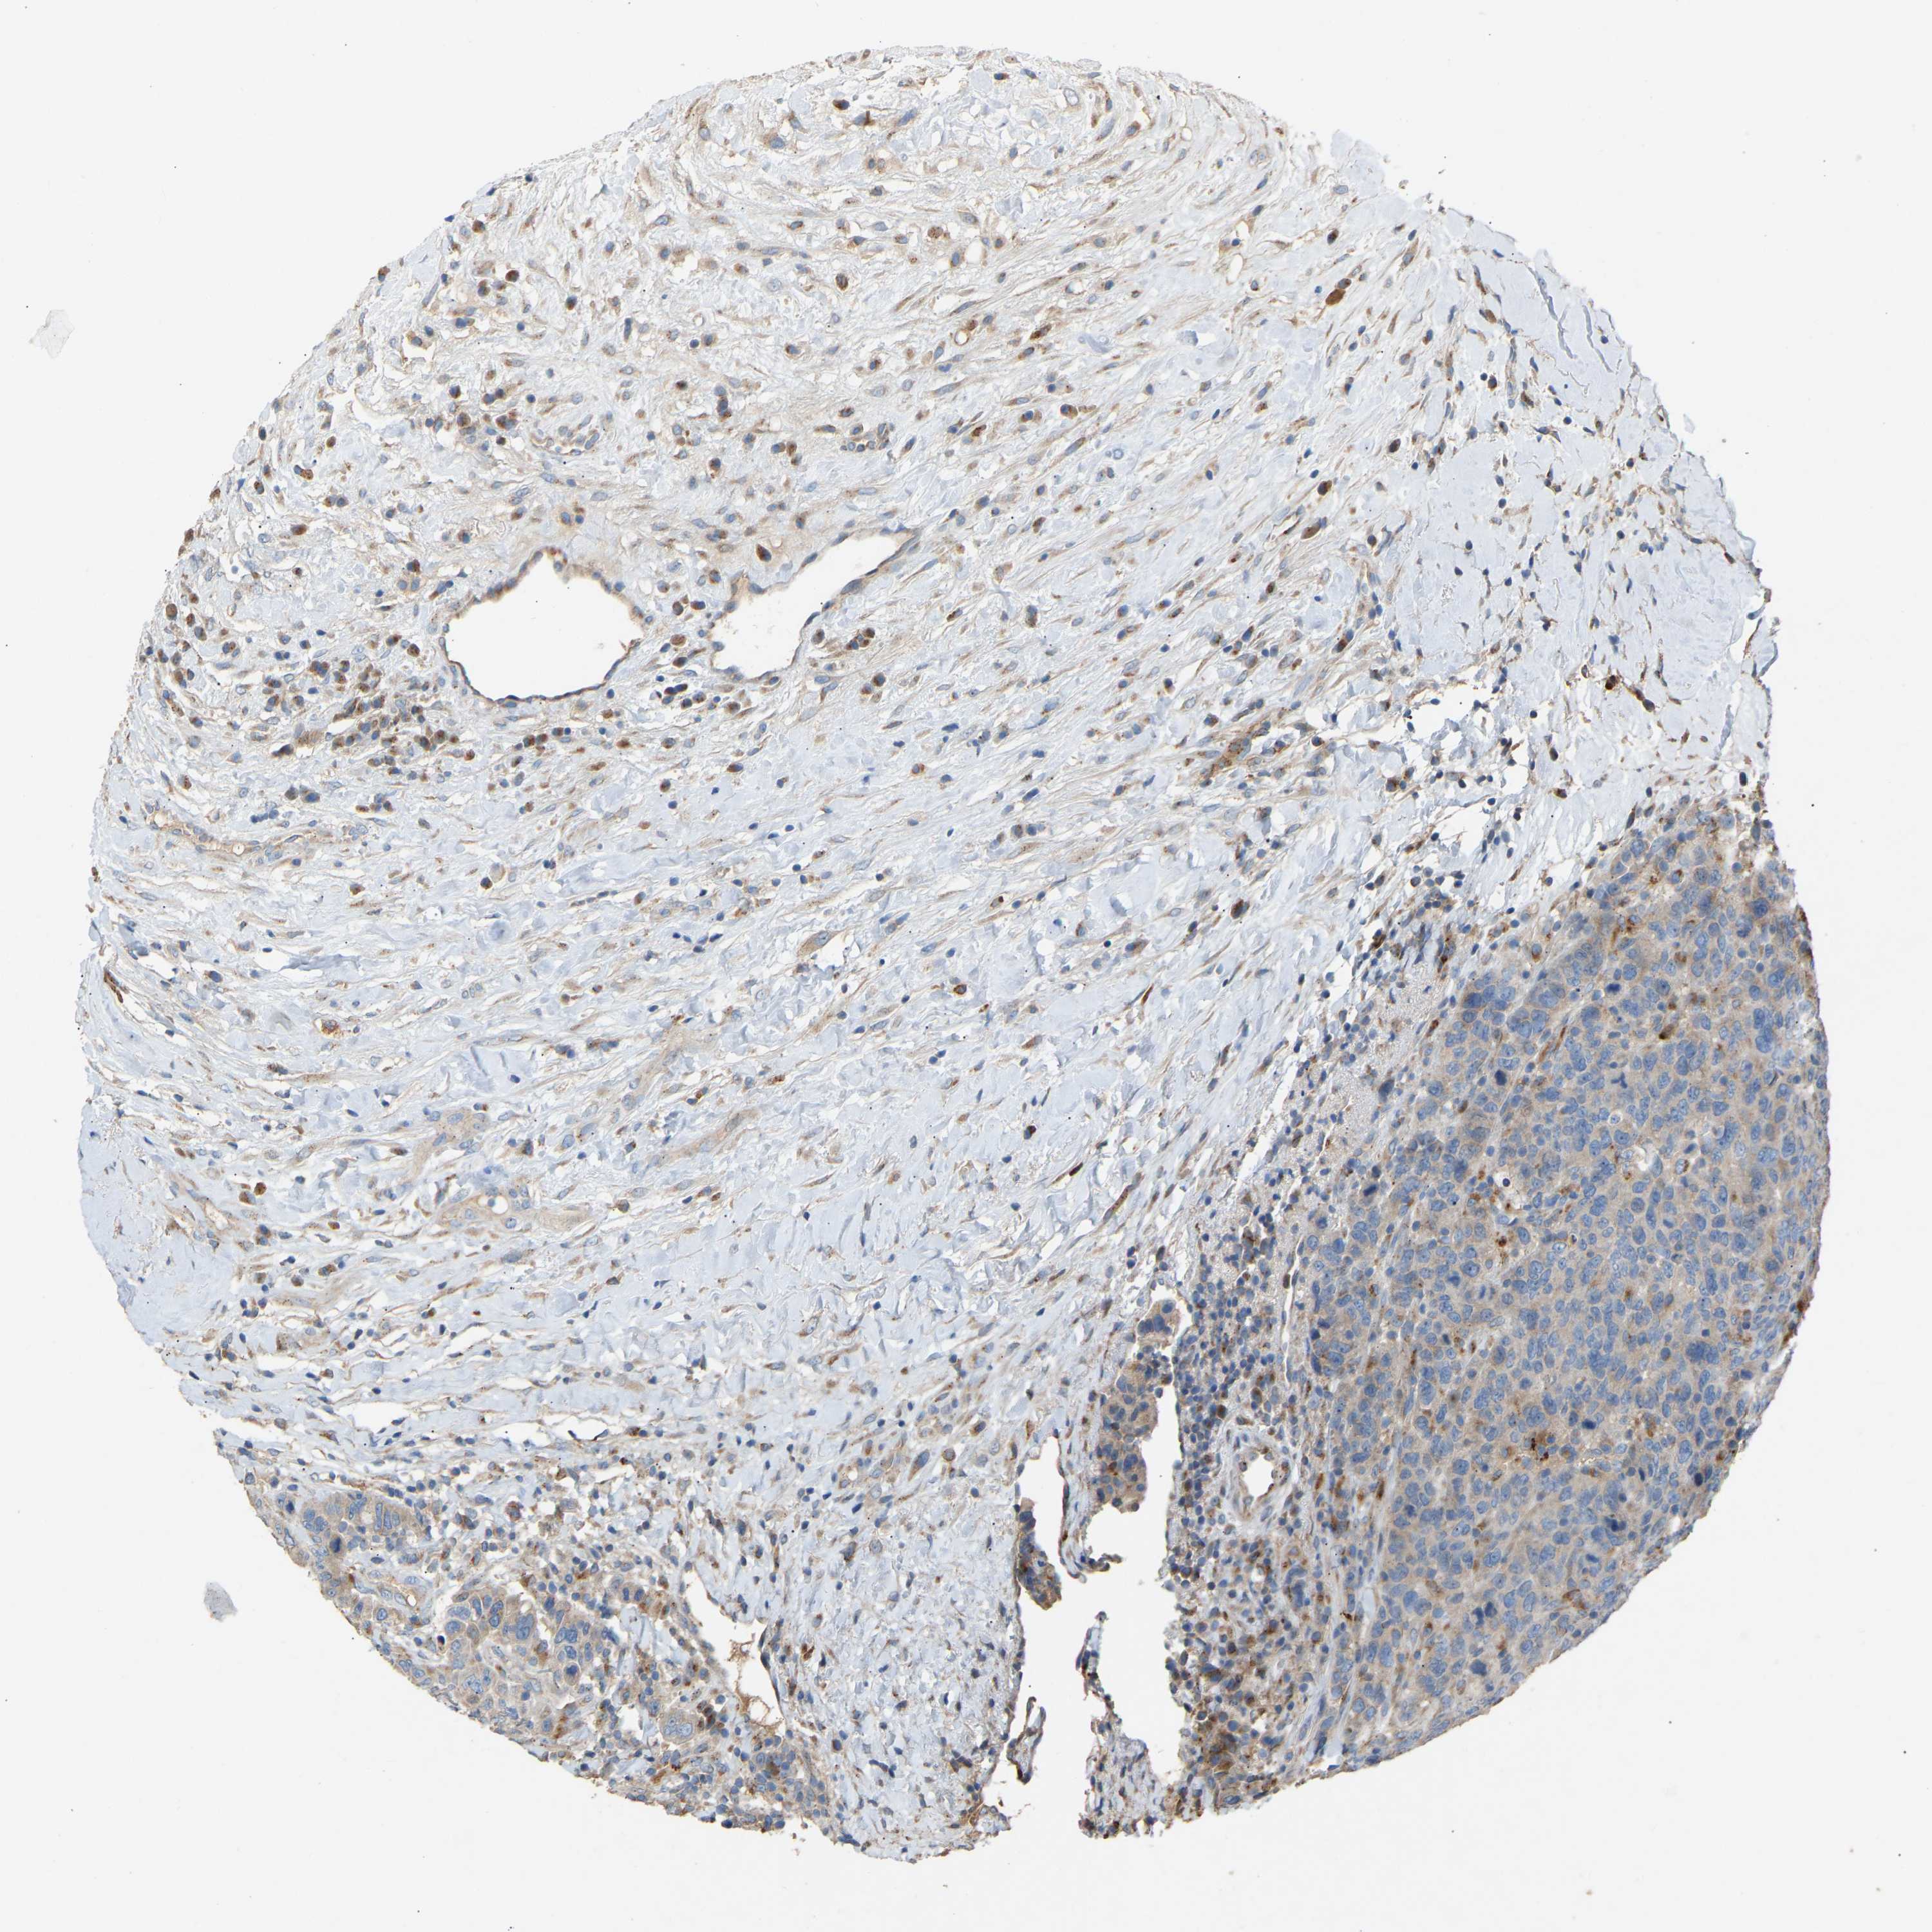

BRCA TCGA BRCA VALIDATION PROTEIN EXPRESSION

ANTIBODIES

AND

VALIDATION